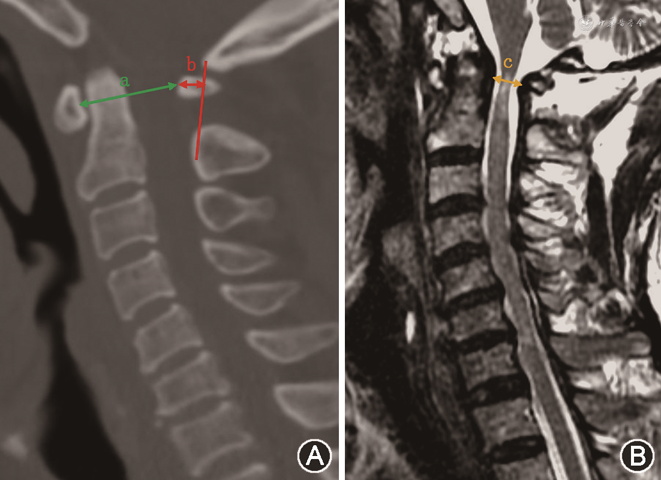

对两组术前影像学资料进行了如下测量。在CT中矢状面重建图像上测量以下数据:寰椎椎管中矢状径:寰椎前结节后缘至后结节前缘的最短距离;寰椎后结节垂直距离:以枢椎椎板前缘中点到枕骨大孔的前缘划一直线,定义为枕枢连线,随后测量寰椎后结节前缘到枕枢连线的垂直距离,定义为寰椎后结节垂直距离。在MRI T2加权像的中矢状面图像上,测量寰椎椎管有效径:枢椎齿状突后缘至寰椎后结节前缘的最短距离,以评估椎管内脊髓的受压情况(图1)。

小寰椎组寰椎椎管中矢状径为(26.4±3.1)mm,对照组为(29.6±2.2)mm,两组差异有统计学意义(t=4.40,P=0.010)。小寰椎组寰椎后结节垂直距离为(6.79±1.17)mm,对照组为(5.57±1.29)mm,两组差异有统计学意义(t=-3.33,P=0.001)。小寰椎组寰椎椎管有效径为(8.25±1.44)mm,对照组为(13.00±1.66)mm,两组差异有统计学意义(t=10.17,P<0.001)。